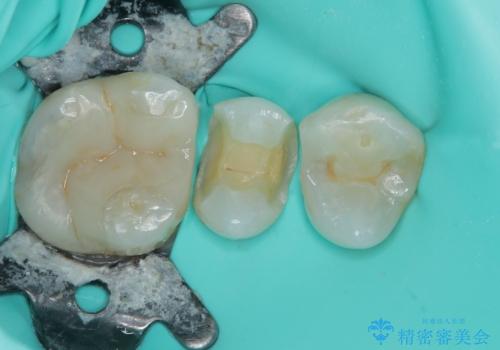

まず、欠けていた詰め物と、その下に存在していた虫歯をすべて丁寧に除去しました。その後、適合性・耐久性・審美性に優れたセラミックインレーを用いて修復処置を行いました。